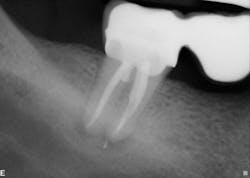

The six-month recall showed nearly complete bone and furcation healing (figure 2). There is still some attachment loss on the straight buccal, but no. 31 remains asymptomatic and in good service.